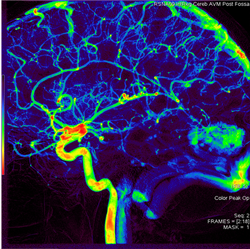

AngioViz uses peak time and density with color as time, and peak density as brightness to show contrast flow timing and magnitud

In one image, AngioViz can show peak pixel density value over an image series. This can indicate relative contrast density and d

AngioViz can show the time that each pixel reaches peak density on a color coded time scale. This helps indicate contrast flow t

AngioViz provides a new visualization of the vascular flow seen in DSA imaging, utilizing a technique called parametric imaging. AngioViz looks at each pixel in the image series and determines two things — the peak value of opacification caused by the contrast, and the time it takes for that pixel to reach peak opacification. These two parameters can be displayed as separate images or combined into a single color-coded image that represents parameters of vascular flow. This enables doctors to perceive parameters of flow quickly to support decision-making. In addition, AngioViz allows easy comparison of parametric images from different DSA acquisitions, such as pre- and post-treatment images. This can help physicians understand the impact on flow dynamics of various interventional treatments.